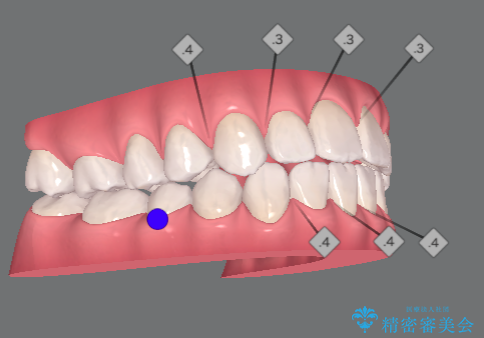

- 前歯の目立つねじれを矯正治療で治したい、と来院されました。

マウスピース矯正を始める前に、ねじれを取るのが短期間で済む部分ワイヤー小矯正を行うことで、全体的な治療期間を短くする治療計画を実行していきます。

前歯のねじれはマウスピース矯正の苦手な動きになり、治療期間が長くなる原因になりやすいです。